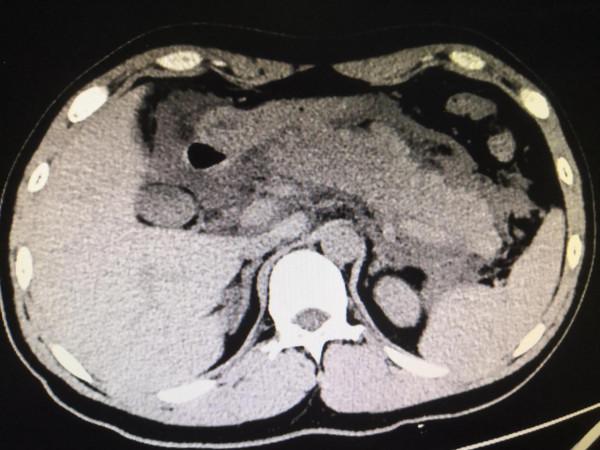

我跟過去做的,CT一掃下來,我就想到急性出血性胰腺炎。

回來診斷性腹穿抽出粉紅色腹水,送檢。